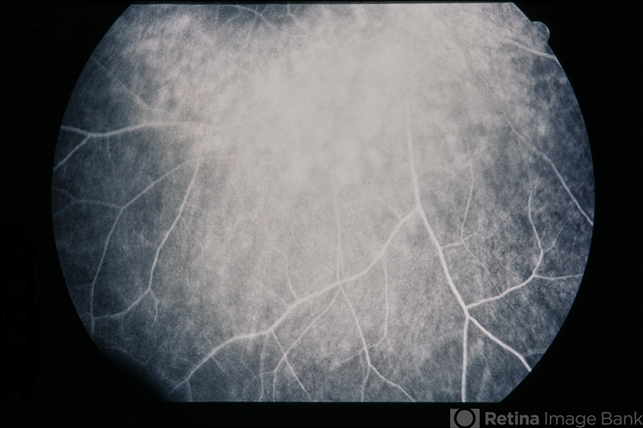

- Plaquenil Toxicity

- 60-year-old female with plaquenil toxicity.